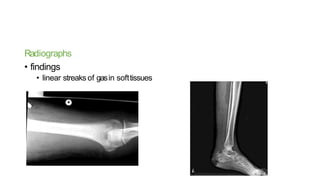

Radiographs

• findings

• linear streaks of gasin softtissues

Radiographs • findings • linearstreaks of gasin softtissues